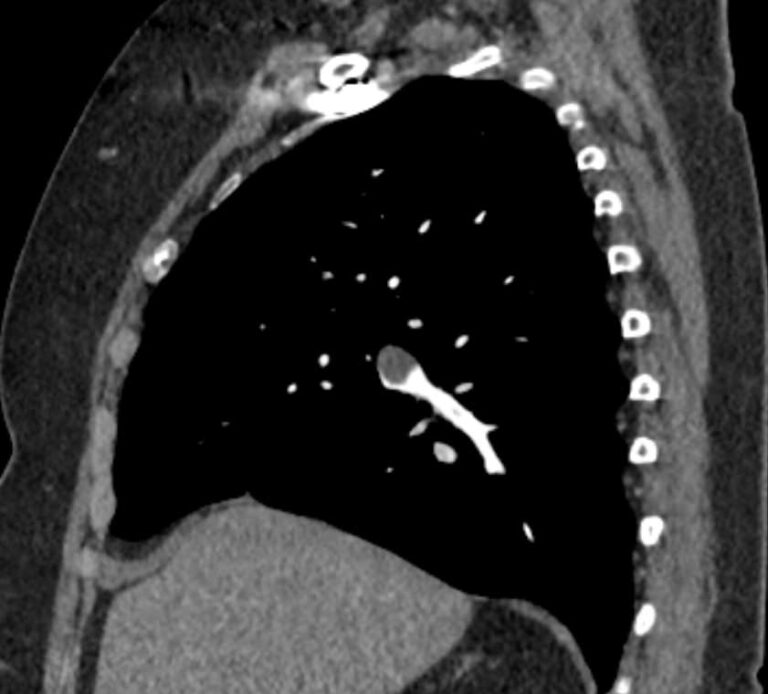

Наиболее информативным, при этом быстрым и неинвазивным (то есть без вмешательства в организм пациента), методом диагностики патологии легочной артерии является мультиспиральная компьютерная томография (КТ-ангиография). Методика основана на использовании рентгеновского излучения в сочетании с цифровой обработкой данных для получения трехмерных изображений сосудистой системы.

Для визуализации кровеносных сосудов в обязательном порядке применяется контрастное усиление. Для этого в вену пациента вводится йодсодержащий контрастный препарат, который попадая в кровоток активно поглощает рентгеновские лучи и ярко контрастирует сосудистую систему, в том числе легочной артерии, на фоне окружающих тканей. Использование контраста дает возможность визуализировать даже мелкие артерии и выявить патологию.

В наших диагностических центрах КТ-ангиография легочной артерии проводится на современных мультиспиральных компьютерных томографах экспертного уровня TOSHIBA AQUILION. Оснащение аппаратов позволяет получать детальные снимки и трехмерные изображения сосудистой системы легочной артерии, при этом применение скоростной мультисрезовой методики сканирования значительно снижает уровень лучевой нагрузки на пациента.